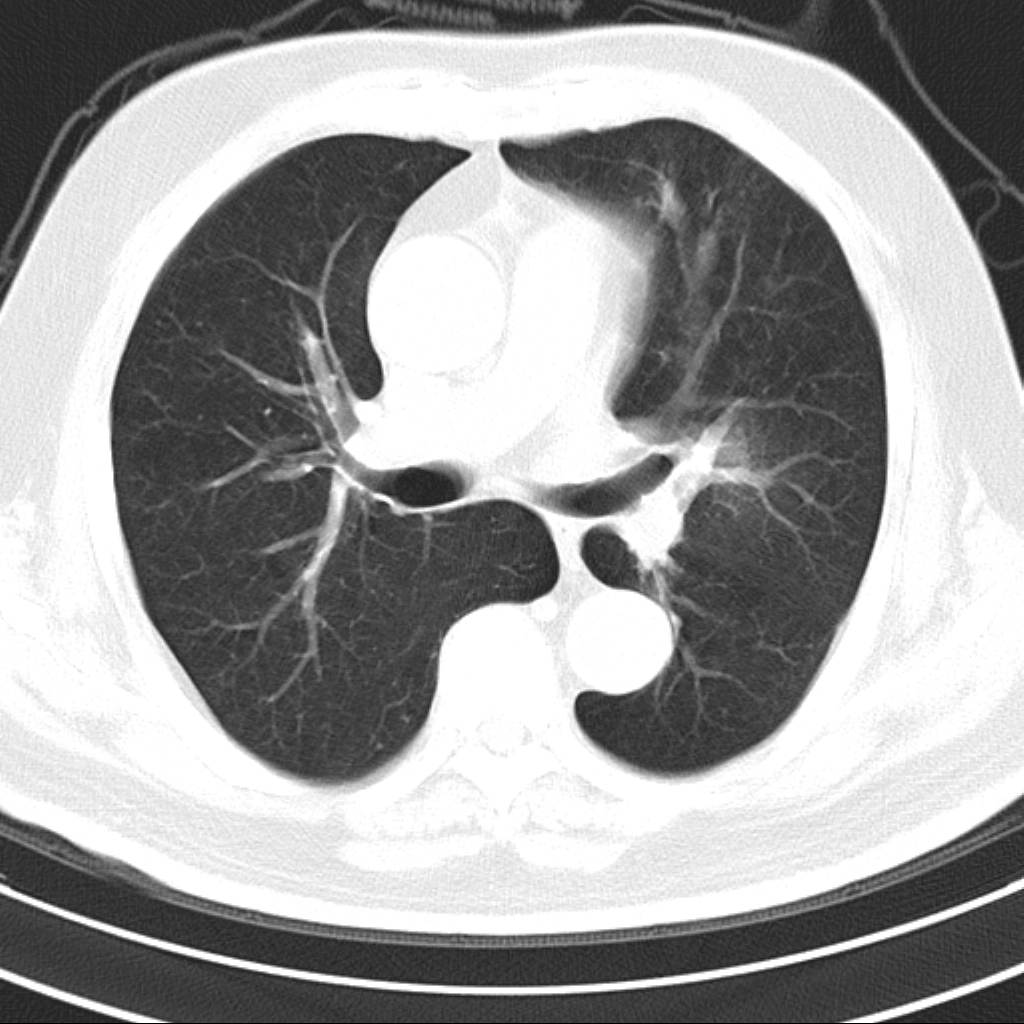

标题: CT18644:男,82岁,体检发现左肺阴影. [打印本页]

标题: CT18644:男,82岁,体检发现左肺阴影.

岁数太大,没有增强。麻烦见过的,给个诊断,顺便再说说病因

左侧中心型肺癌并粘液栓形成。很典型的。手套征。

支持 左肺上叶中央型肺癌并支气管内粘液栓形成。

尚不除外非感染炎症,过敏及哮喘曲霉菌病所致黏液栓塞,纸套征比较形象妾有一定特异性

考虑左肺上叶中央型肺癌并支气管内粘液栓形成。

支持 左肺上叶中央型肺癌并支气管内粘液栓形成,阻塞性肺炎

考虎左肺上叶中央型肺癌并支气管内黏液栓形成,不能增强是个遗憾,期待复查结果。

左肺上叶中央型肺癌